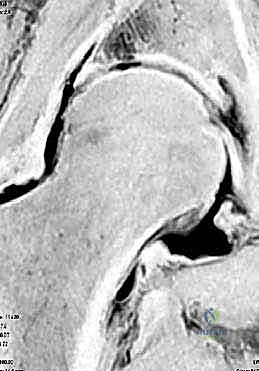

- الرنين المغناطيسي (MRI / MR Arthrogram): يُعد الرنين المغناطيسي مع حقن الصبغة داخل المفصل هو الفحص الذهبي لرؤية الأنسجة الرخوة مثل الشفا الغضروفي والغضاريف المفصلية بدقة شديدة.

يُغطى كل من الكرة والتجويف بطبقة ناعمة من الغضروف المفصلي الذي يسمح للعظام بالانزلاق بسلاسة فوق بعضها البعض. كما يحيط بحافة التجويف حلقة من الغضروف الليفي القوي تُسمى الشفا الغضروفي (Labrum). يعمل الشفا كختم مطاطي يحافظ على السائل الزلالي داخل المفصل ويزيد من استقراره.

وهي حالة شائعة جداً تحدث عندما تنمو نتوءات عظمية زائدة إما على رأس عظمة الفخذ (Cam) أو على حافة تجويف الحوض (Pincer)، أو كليهما. هذا النمو الزائد يؤدي إلى احتكاك غير طبيعي أثناء الحركة، مما يمزق الشفا الغضروفي ويتلف الغضروف المفصلي.

2. تمزق الشفا الغضروفي (Labral Tears)

الشفا الغضروفي هو الحلقة التي تحافظ على استقرار المفصل. يمكن أن يتمزق بسبب الإصابات الرياضية (مثل الجمباز، كرة القدم، أو الفنون القتالية) أو بسبب حالة الاصطدام الفخذي الحقي. بالمنظار، يتم خياطة هذا التمزق وتثبيته بخطاطيف دقيقة جداً (Suture Anchors).